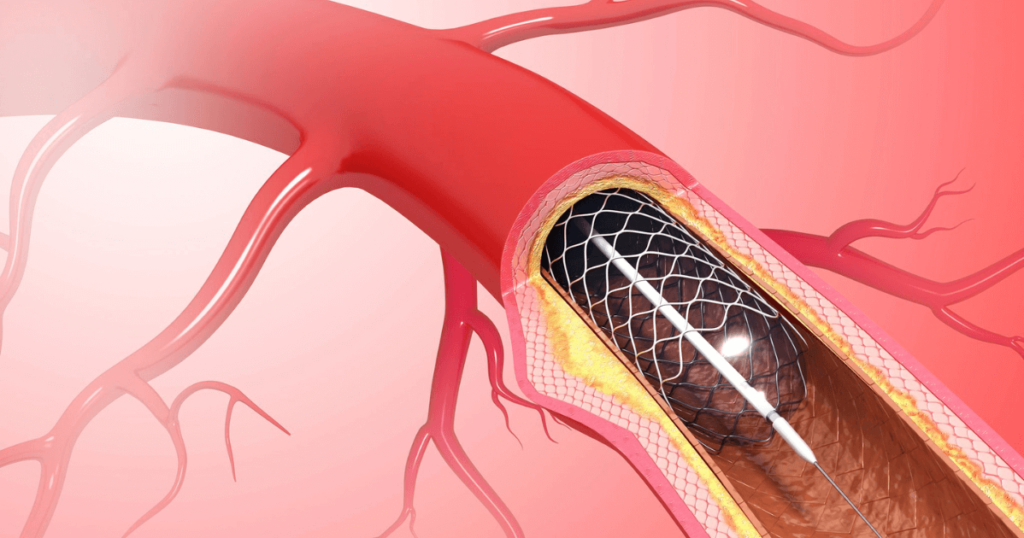

By combining high-resolution CT technology with an intravenous contrast agent, CTCA produces detailed 3D images of the heart vessels, allowing precise evaluation of blockages, vessel narrowing, plaque burden, and calcium deposits-often before symptoms become severe.

During the procedure, contrast dye is administered through a peripheral vein, while a high-speed CT scanner captures images synchronized with the cardiac cycle.

This advanced timing significantly reduces motion artifacts and ensures clear visualization of even small coronary branches.

Unlike conventional catheter-based angiography, CTCA does not involve arterial puncture or hospital admission. As a result, the scan is safer, quicker, and far more comfortable for patients, while still maintaining excellent diagnostic accuracy.

CT Coronary Angiography and conventional angiography differ primarily in approach and clinical use. CTCA is non-invasive, requires no catheter insertion, and is ideal for ruling out coronary artery disease in low- to intermediate-risk patients.

In contrast, conventional angiography is an invasive procedure typically reserved for cases where immediate intervention, such as angioplasty or stenting, is required. Therefore, CTCA is often recommended as a first-line diagnostic tool, helping clinicians avoid unnecessary invasive procedures while ensuring accurate cardiac assessment.